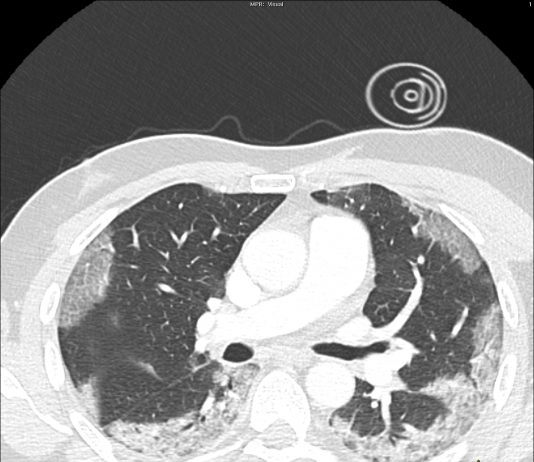

57-year-old male patient with fever, cough. No previous medical history. Potential exposure to Covid-19 patients.

Respiratory

failure (hypoxemia and hypocapnia). Leukocitosi. Nasal swab positive for

SARS-CoV-2.

HRCT